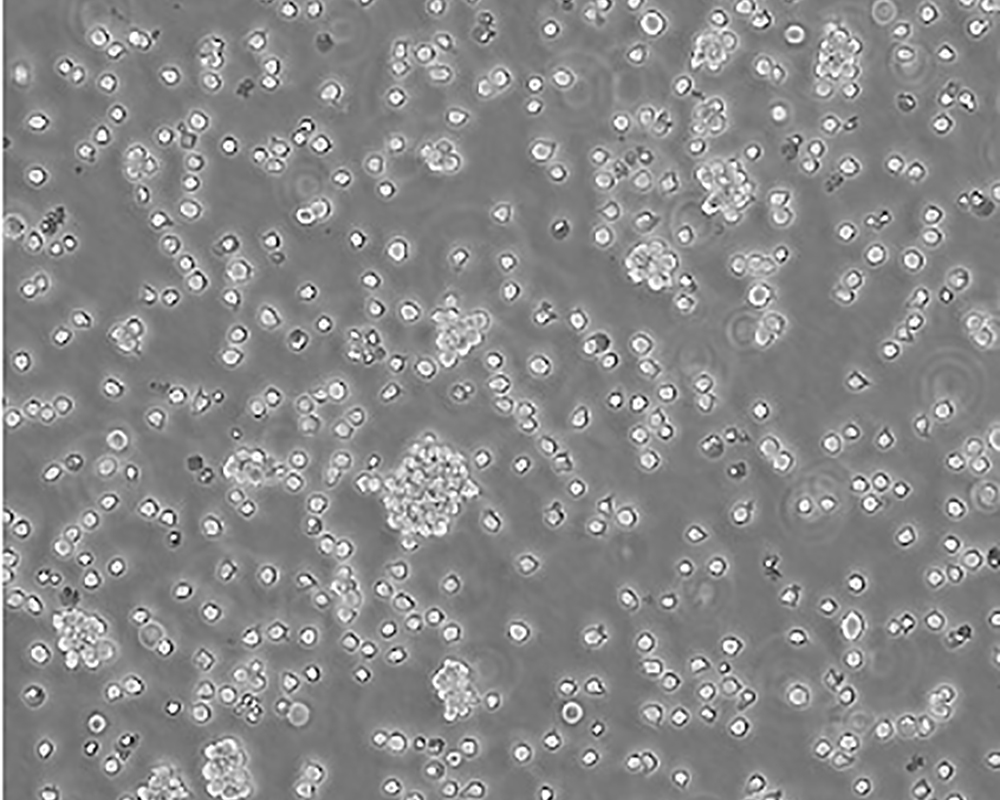

Jurkat, Clone E6-1 [Jurkat E6-1]

人T淋巴細胞白血病細胞

急性T淋巴細胞白血病;男性

Homo sapiens, human

suspension

lymphoblast

該細胞是Jurkat-FHCRC細胞株(Jurkat細胞株的衍生)的一個克隆。Jurkat細胞株來源于一個14歲男孩的外周血。經佛波酯和外源凝集素或抗T3單克隆抗體誘導后可產生大量IL-2(IL-2的產生需兩種類型的誘導劑);表達T細胞受體、CD3